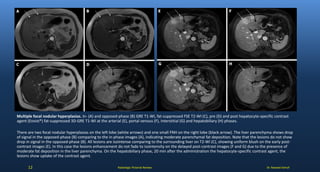

Multiple focal nodular hyperplasias. In- (A) and opposed-phase (B) GRE T1-WI, fat-suppressed FSE T2-WI (C), pre (D) and post hepatocyte-specific contrast

agent (Eovist®) fat-suppressed 3D-GRE T1-WI at the arterial (E), portal venous (F), interstitial (G) and hepatobiliary (H) phases.

There are two focal nodular hyperplasias on the left lobe (white arrows) and one small FNH on the right lobe (black arrow). The liver parenchyma shows drop

of signal in the opposed-phase (B) comparing to the in-phase images (A), indicating moderate parenchymal fat deposition. Note that the lesions do not show

drop in signal in the opposed-phase (B). All lesions are isointense comparing to the surrounding liver on T2-WI (C), showing uniform blush on the early post-

contrast images (E). In this case the lesions enhancement do not fade to isointensity on the delayed post-contrast images (F and G) due to the presence of

moderate fat deposition in the liver parenchyma. On the hepatobiliary phase, 20 min after the administration the hepatocyte-specific contrast agent, the

lesions show uptake of the contrast agent.